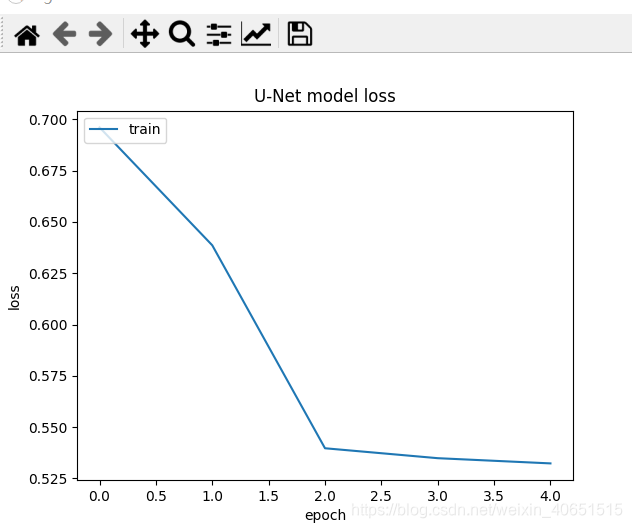

其实验结果的准确率曲线与模型训练次数的曲线如下所示:

从图中我们发现 U-Net模型在经过简化之后,其在细胞分割任务中已经达到了不错的训练效果结果,其准确率高达78%,为了进一步提高模型准确率,我们需要在模型设计环节设计完整的 U-Net模型,并加大模型的训练次数,这样就能使模型很轻松的达到95%左右。